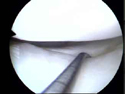

χόνδρο και τους μηνίσκους. Η αποκατάσταση των ρήξεων αυτών γίνεται

με τη χρήση των κάτωθι μοσχευμάτων:

Η χρήση αυτού του μόσχευματος μας πρόσφέρει ένα πολύ ισυρό μόσχευμα

που επιτρέπει την αποκατάσταση και των δύο μοίρων του φυσιολογικού

οπισθίου χιαστού συνδέσμου. Έτσι περισσεύει το τενόντιο μόσχευμα

(Hamstrings) και μπορεί να χρησιμοποιηθεί για την αποκατάσταση

της βλάβης της οπίσθιας έξω γωνίας.